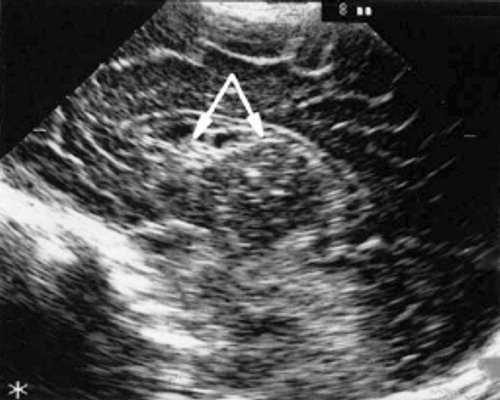

При эхоэнцефалографии у детей I группы выявлено от 1 до 3 изолированных кистозных структур (не сочетающихся с другими структурными изменениями) диаметром от 0,2-0,5 см (рис. 1, 2), расположенных в верхушке или теле сосудистого сплетения левого бокового желудочка. У 3-х из этих детей исходные данные вентрикулометрии соответствовали нормальным значениям. У 1-го ребенка отмечено незначительное (до 0,6 см) расширение межполушарной щели и субарахноидальных пространств по конвекситальной поверхности мозга и умеренное симметричное увеличение ширины лобных рогов (преимущественно) и высоты тел боковых желудочков (до 0,7 см).

Рис. 1. Эхоэнцефалограмма ребенка Р. со смешанной герпес-цитомегаловирусной инфекцией, 7-е сут. жизни. Стрелками обозначена киста в верхушке сосудистого сплетения левого бокового желудочка.